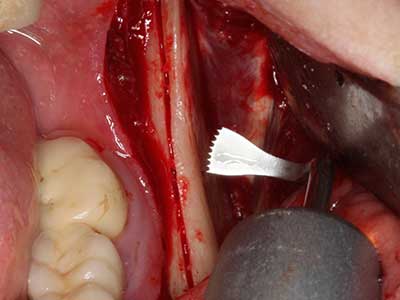

Sollen chirurgische Eingriffe mit unmittelbarer Knochenbeziehung an empfindlichen Strukturen wie Blutgefäßen oder Nerven erfolgen, so bergen rotierende Instrumente ein erhebliches Potential an iatrogener Schädigung. Gerade bei Nervdarstellungen nach iatrogener Schädigung, oder aber im Zuge einer Nervlateralisation für resektive und rekonstruktive Eingriffe oder Implantatinsertionen können piezoelektronische Geräte hilfreich sein Knochendeckel zu präparieren und nervnahe Hartgewebsanteile zu entfernen (Abb. 17-20). Ein leichter Kontakt des Nervstrangs zur Piezospitze bleibt dabei in der Regel folgenlos – allerdings kann eine unvorsichtige Vorgehensweise mit sägeartigen Bewegungen bzw. Ansätzen bei noch vorhandener knöcherner Unterlage durchaus temporäre oder aber auch permanente Nervschädigungen verursachen. Das Risiko einer solchen Schädigung wird jedoch als wesentliche geringer eingeschätzt als unter Anwendung von Säge- oder Fräsinstrumenten (Pereira, Gealh et al. 2014).

Indikation: Wurzelspitzenresektion